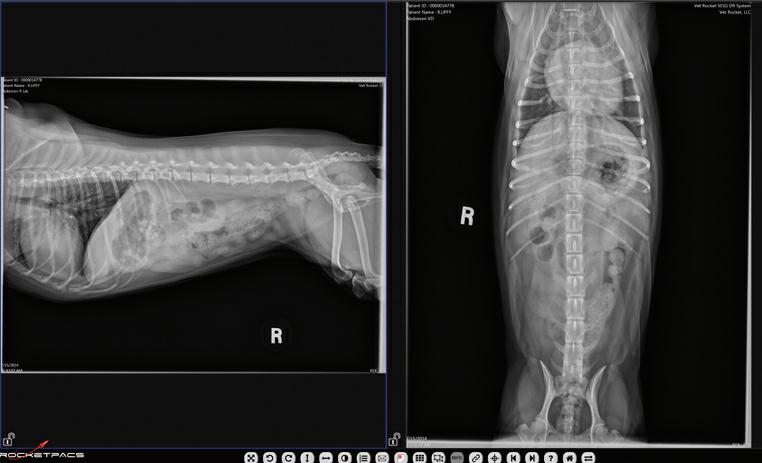

Uretral Stenting Surgery at the Centre for Animal Referral & Emergency (CARE)

Ureteral obstruction is increasingly recognised as a cause of acute renal dysfunction in cats. Fortunately, there is a range of options for renal decompression using tubing, or stents, to divert urine past the site of obstruction to external collection systems (percutaneous nephrostomy) or to the bladder, placed either within the ureter (endoluminal) or external to it (Subcutaneous Ureteral Bypass). Dr Guy Yates and the surgery team at CARE regularly perform ureteral stenting surgery and have recently published an evolution of a common stenting procedure that minimises postoperative complications and simplifies surgical placement. Many factors influence the post-operative prognosis, however, re-establishment of urine flow from the kidney preserves renal function and achieves a favourable outcome in many patients.